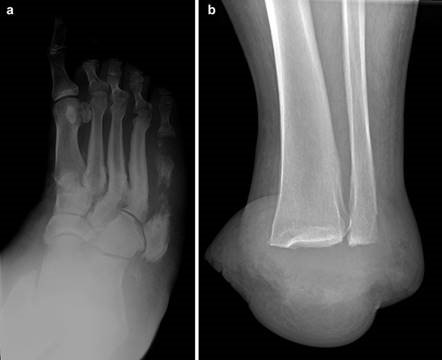

Clinical & Radiographic Imaging Archive

Clinical Image